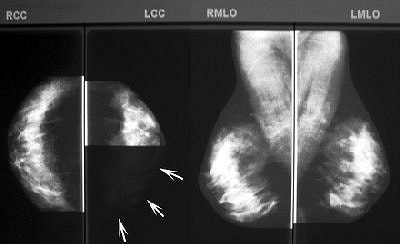

| Bilateral CAD images in a 54-year-old woman demonstrate unacceptable segmentation of breast parenchyma. Left: Craniocaudal CAD image. CAD segmentation excluded 50% of breast parenchyma (arrows). Right: Mediolateral oblique CAD image demonstrates near-perfect segmentation. Baker JA, Rosen EL, Crockett MM, Lo JY, "Accuracy of Segmentation of a Commercial Computer-aided Detection System for Mammography," Radiology 2005:235(2):385-390. doi:10.1148/radiol.2352040899. Published March 15, 2005; accessed April 7, 2005. |

Overall, segmentation was near-perfect or acceptable in 96.8% of the cases and unacceptable in 6.2%. Similar results were achieved for mammograms that were categorized as fatty replaced or scattered fibroglandular tissue (98.2% near-perfect or acceptable for the latter). The area of excluded tissue averaged 24.7%.

In heterogeneously dense breasts, only 92% of the exams were considered near-perfect or acceptable; 8% were unacceptable. "This level of unacceptable segmentation for heterogeneously dense breasts is over five times the 1.4% unacceptable rate for the other three categories of breast density combined," the authors stated.